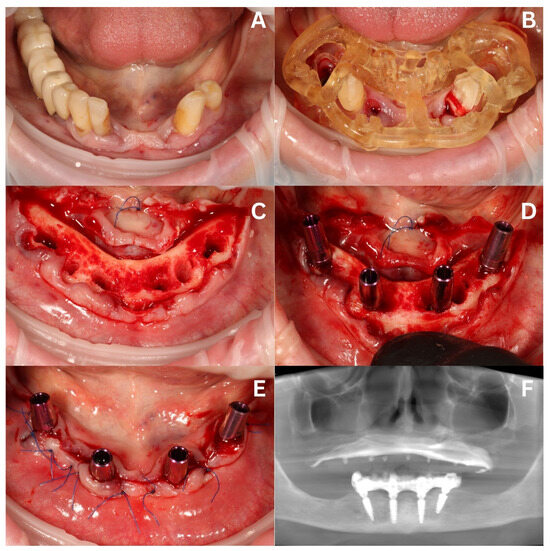

3.2. Surgery in the Mandible and Immediate Loading—Stage I